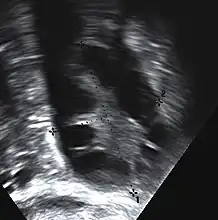

-

Transvaginal ultrasound scan of polycystic ovary -

Polycystic ovary as seen on sonography

The syndrome acquired its most widely used name due to the common sign on ultrasound examination of multiple (poly) ovarian cysts. These "cysts" are actually immature follicles not cysts. The follicles have developed from primordial follicles, but the development has stopped ("arrested") at an early antral stage due to the disturbed ovarian function. The follicles may be oriented along the ovarian periphery, appearing as a 'string of pearls' on ultrasound examination.

- Gynecologic ultrasonography, specifically looking for small ovarian follicles. These are believed to be the result of disturbed ovarian function with failed ovulation, reflected by the infrequent or absent menstruation that is typical of the condition. In a normal menstrual cycle, one egg is released from a dominant follicle – in essence, a cyst that bursts to release the egg. After ovulation, the follicle remnant is transformed into a progesterone-producing corpus luteum, which shrinks and disappears after approximately 12–14 days. In PCOS, there is a so-called "follicular arrest"; i.e., several follicles develop to a size of 5–7 mm, but not further. No single follicle reaches the preovulatory size (16 mm or more). According to the Rotterdam criteria, which are widely used for diagnosis,[10] 12 or more small follicles should be seen in an ovary on ultrasound examination.[58] More recent research suggests that there should be at least 25 follicles in an ovary to designate it as having polycystic ovarian morphology (PCOM) in women aged 18–35 years.[64] The follicles may be oriented in the periphery, giving the appearance of a 'string of pearls'.[65] If a high resolution transvaginal ultrasonography machine is not available, an ovarian volume of at least 10 ml is regarded as an acceptable definition of having polycystic ovarian morphology instead of follicle count.[64]

Ultrasound findings in PCOS include enlarged ovaries with peripheral follicles in a "string of pearls" configuration.